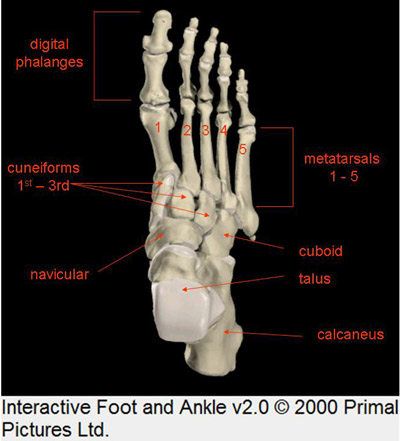

Os locais, foram:

abaixo do maléolo medial,

no lado de dentro do pé,

no peito do pé,

no começo dos dedos menores,

e na planta do pé, lugar do "Plexo

Solar".